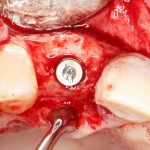

Кстати, обрати внимание на ширину альвеолярного гребня (левая картинка). Она чуть меньше 3 мм. Это объясняет, почему я засомневался в возможности установки имплантатов одновременно с остеопластикой. Понятно и без КЛКТ.

Возвращаемся к основной операционной области. Еще раз посмотрим на альвеолярный гребень, поофигеваем от его ширины и моих грандиозных планов:

Я зафиксировал костный блок практически без адаптации на несколько винтов. Обрати внимание, что винты находятся в зоне, где не планируется установка имплантатов. Фиксация должна быть надежной, поскольку мне еще предстояла подготовка лунок для имплантатов. Трех винтов для этого вполне достаточно.

Напомню, что для этой работы я выбрал субкрестальные имплантаты Ankylos C/X. Они прекрасно сочетаются с любым методом остеопластики.

Глянем на то, что получилось: